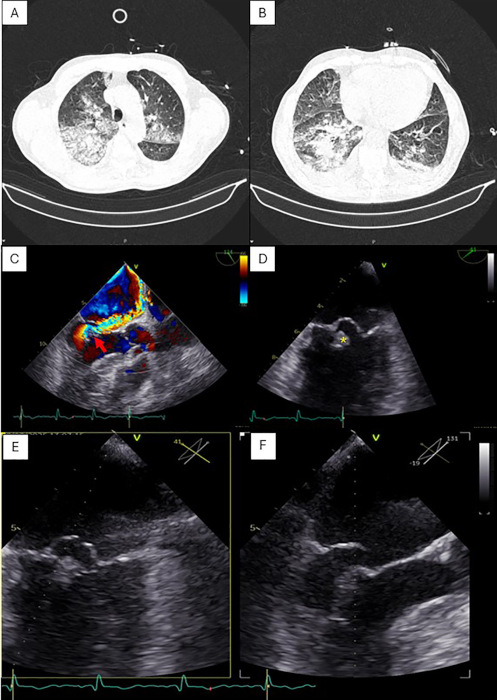

Chest computed tomography (CT) revealed diffuse bilateral ground-glass opacities and crazy-paving pattern, predominantly in the right lung, interpreted as either pneumonia or diffuse PAH (Figure 1A-B). He was initially admitted with suspected pneumonia and empirically started on antibiotics, but rapidly deteriorated with acute hypoxemic respiratory failure, requiring immediate intubation and invasive mechanical ventilation.

Transthoracic and transesophageal echocardiography (TEE) demonstrated preserved left ventricular systolic function with mid-basal inferoposterior hypokinesia, alongside severe, eccentric AMR, with pulmonary vein flow reversal, due to flail of the posterior mitral leaflet, involving P1-P2 scallops, consistent with probable posteromedial PMR (Figure 1C-F). A descending thoracic aortic atherosclerotic plaque with suspected mural thrombus was also noted, later confirmed with CT angiography, along with multiple splenic infarcts. (Fig.2).

Fig. 1

Chest CT scan (A-B) showing diffuse bilateral ground-glass opacities and a crazy-paving pattern, consistent with pulmonary alveolar hemorrhage. Transesophageal echocardiography demonstrating severe eccentric mitral regurgitation (red arrow) through Color Doppler imaging (C) due to flail of the posterior mitral leaflet (P1-P2 scallops), consistent with posteromedial papillary muscle rupture (yellow asterix) (D). Multiplanar views of posterior mitral leaflet flail (E-F).